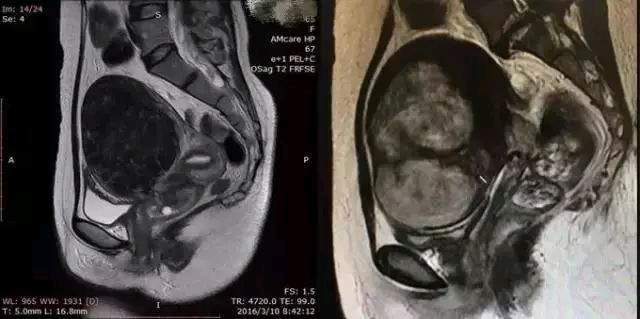

左图为T2低信号肌瘤,适合磁波治疗,

右图为T2高信号肌瘤,若是做磁波治疗,可能效果不佳